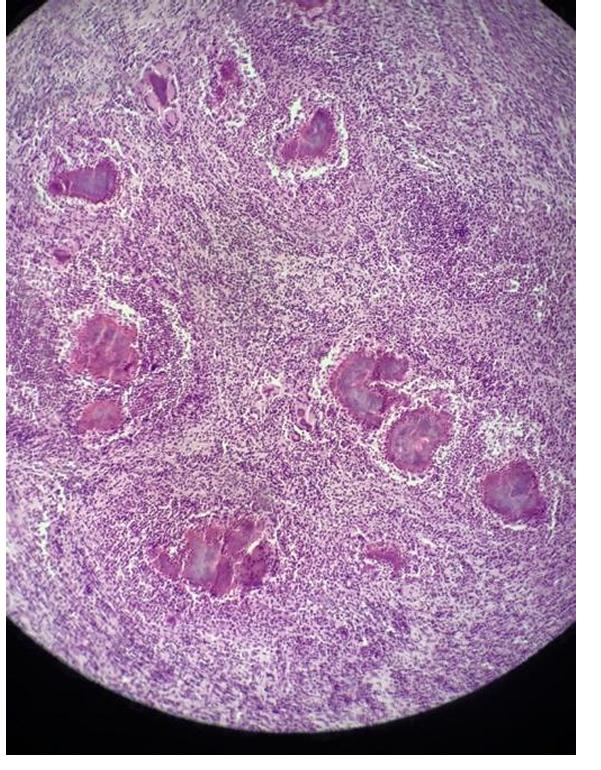

this is?

infectious bursal disease - changes in bursa (side of B-lymph production) of fabricius during infectious bursal disease (gumboro, birnavirus)